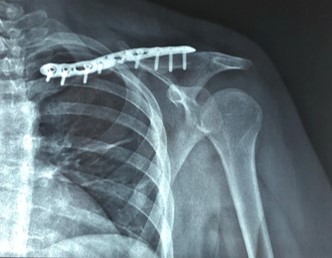

Χειρουργική Θεραπεία

Η χειρουργική αντιμετώπιση ενδείκνυται είτε σε κατάγματα με μεγάλη παρεκτόπιση και συντριβή, είτε επί αποτυχίας της συντηρητικής θεραπείας. Επίσης η χειρουργική αντιμετώπιση κρίνεται αναγκαία για κατάγματα στα οποία το δέρμα κινδυνεύει από την πίεση των οστικών τεμαχίων του κατάγματος. Περιλαμβάνει την ανατομική ανάταξη του καταγματικών τεμαχίων και την οστεοσύνθεσή τους. Πραγματοποιείται υπό γενική αναισθησία και ο ασθενής παίρνει εξιτήριο μετά από κάποιες ώρες ή την επόμενη ημέρα. Ο ασθενής θα φοράει μια ανάρτηση για 4 εβδομάδες, ωστόσο ενθαρρύνεται να κάνει κινήσεις του αγκώνα και του χεριού άμεσα μετεγχειρητικά. Σε συνεργασία με τον θεράποντα φυσικοθεραπευτή δημιουργείται ένα εξατομικευμένο πρόγραμμα με στόχο την ταχύτερη αποκατάσταση του ασθενούς.